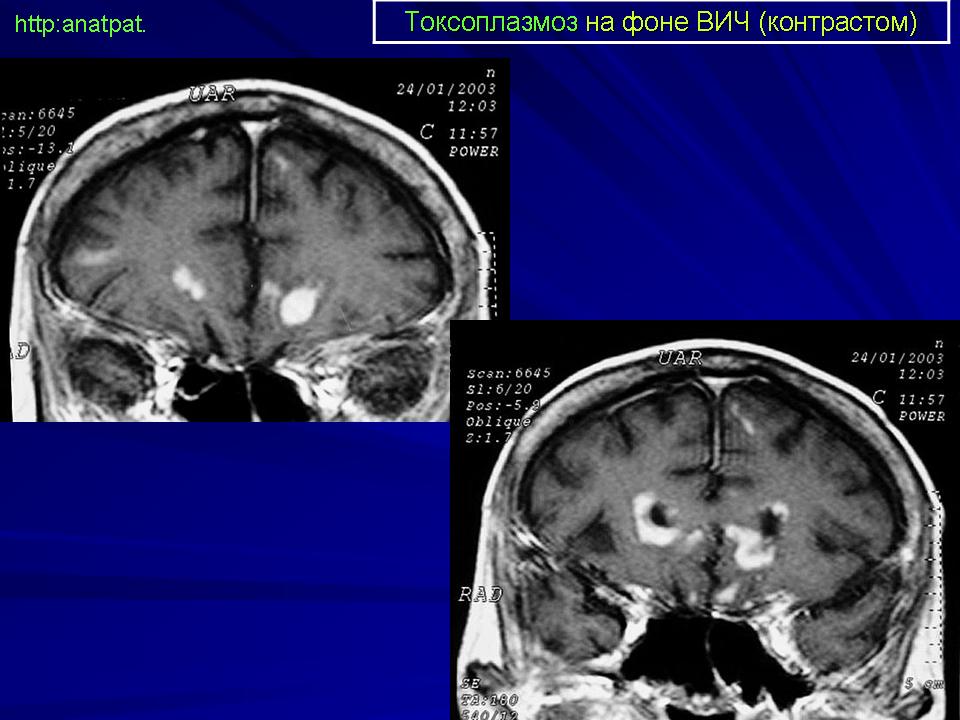

Церебральный токсоплазмоз.

Токсоплазмоз у ВИЧ - инфицированных

Церебральный токсоплазмоз

Neurotoxoplasmosis